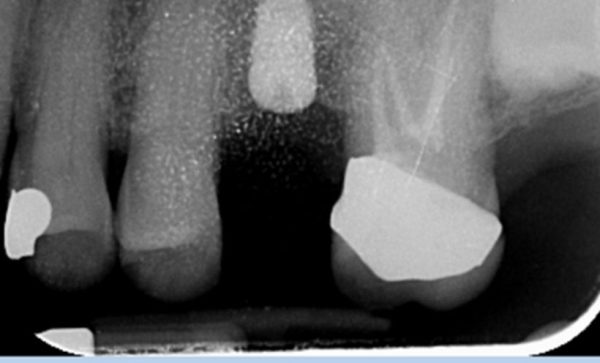

Before Xray - Abacus Dental